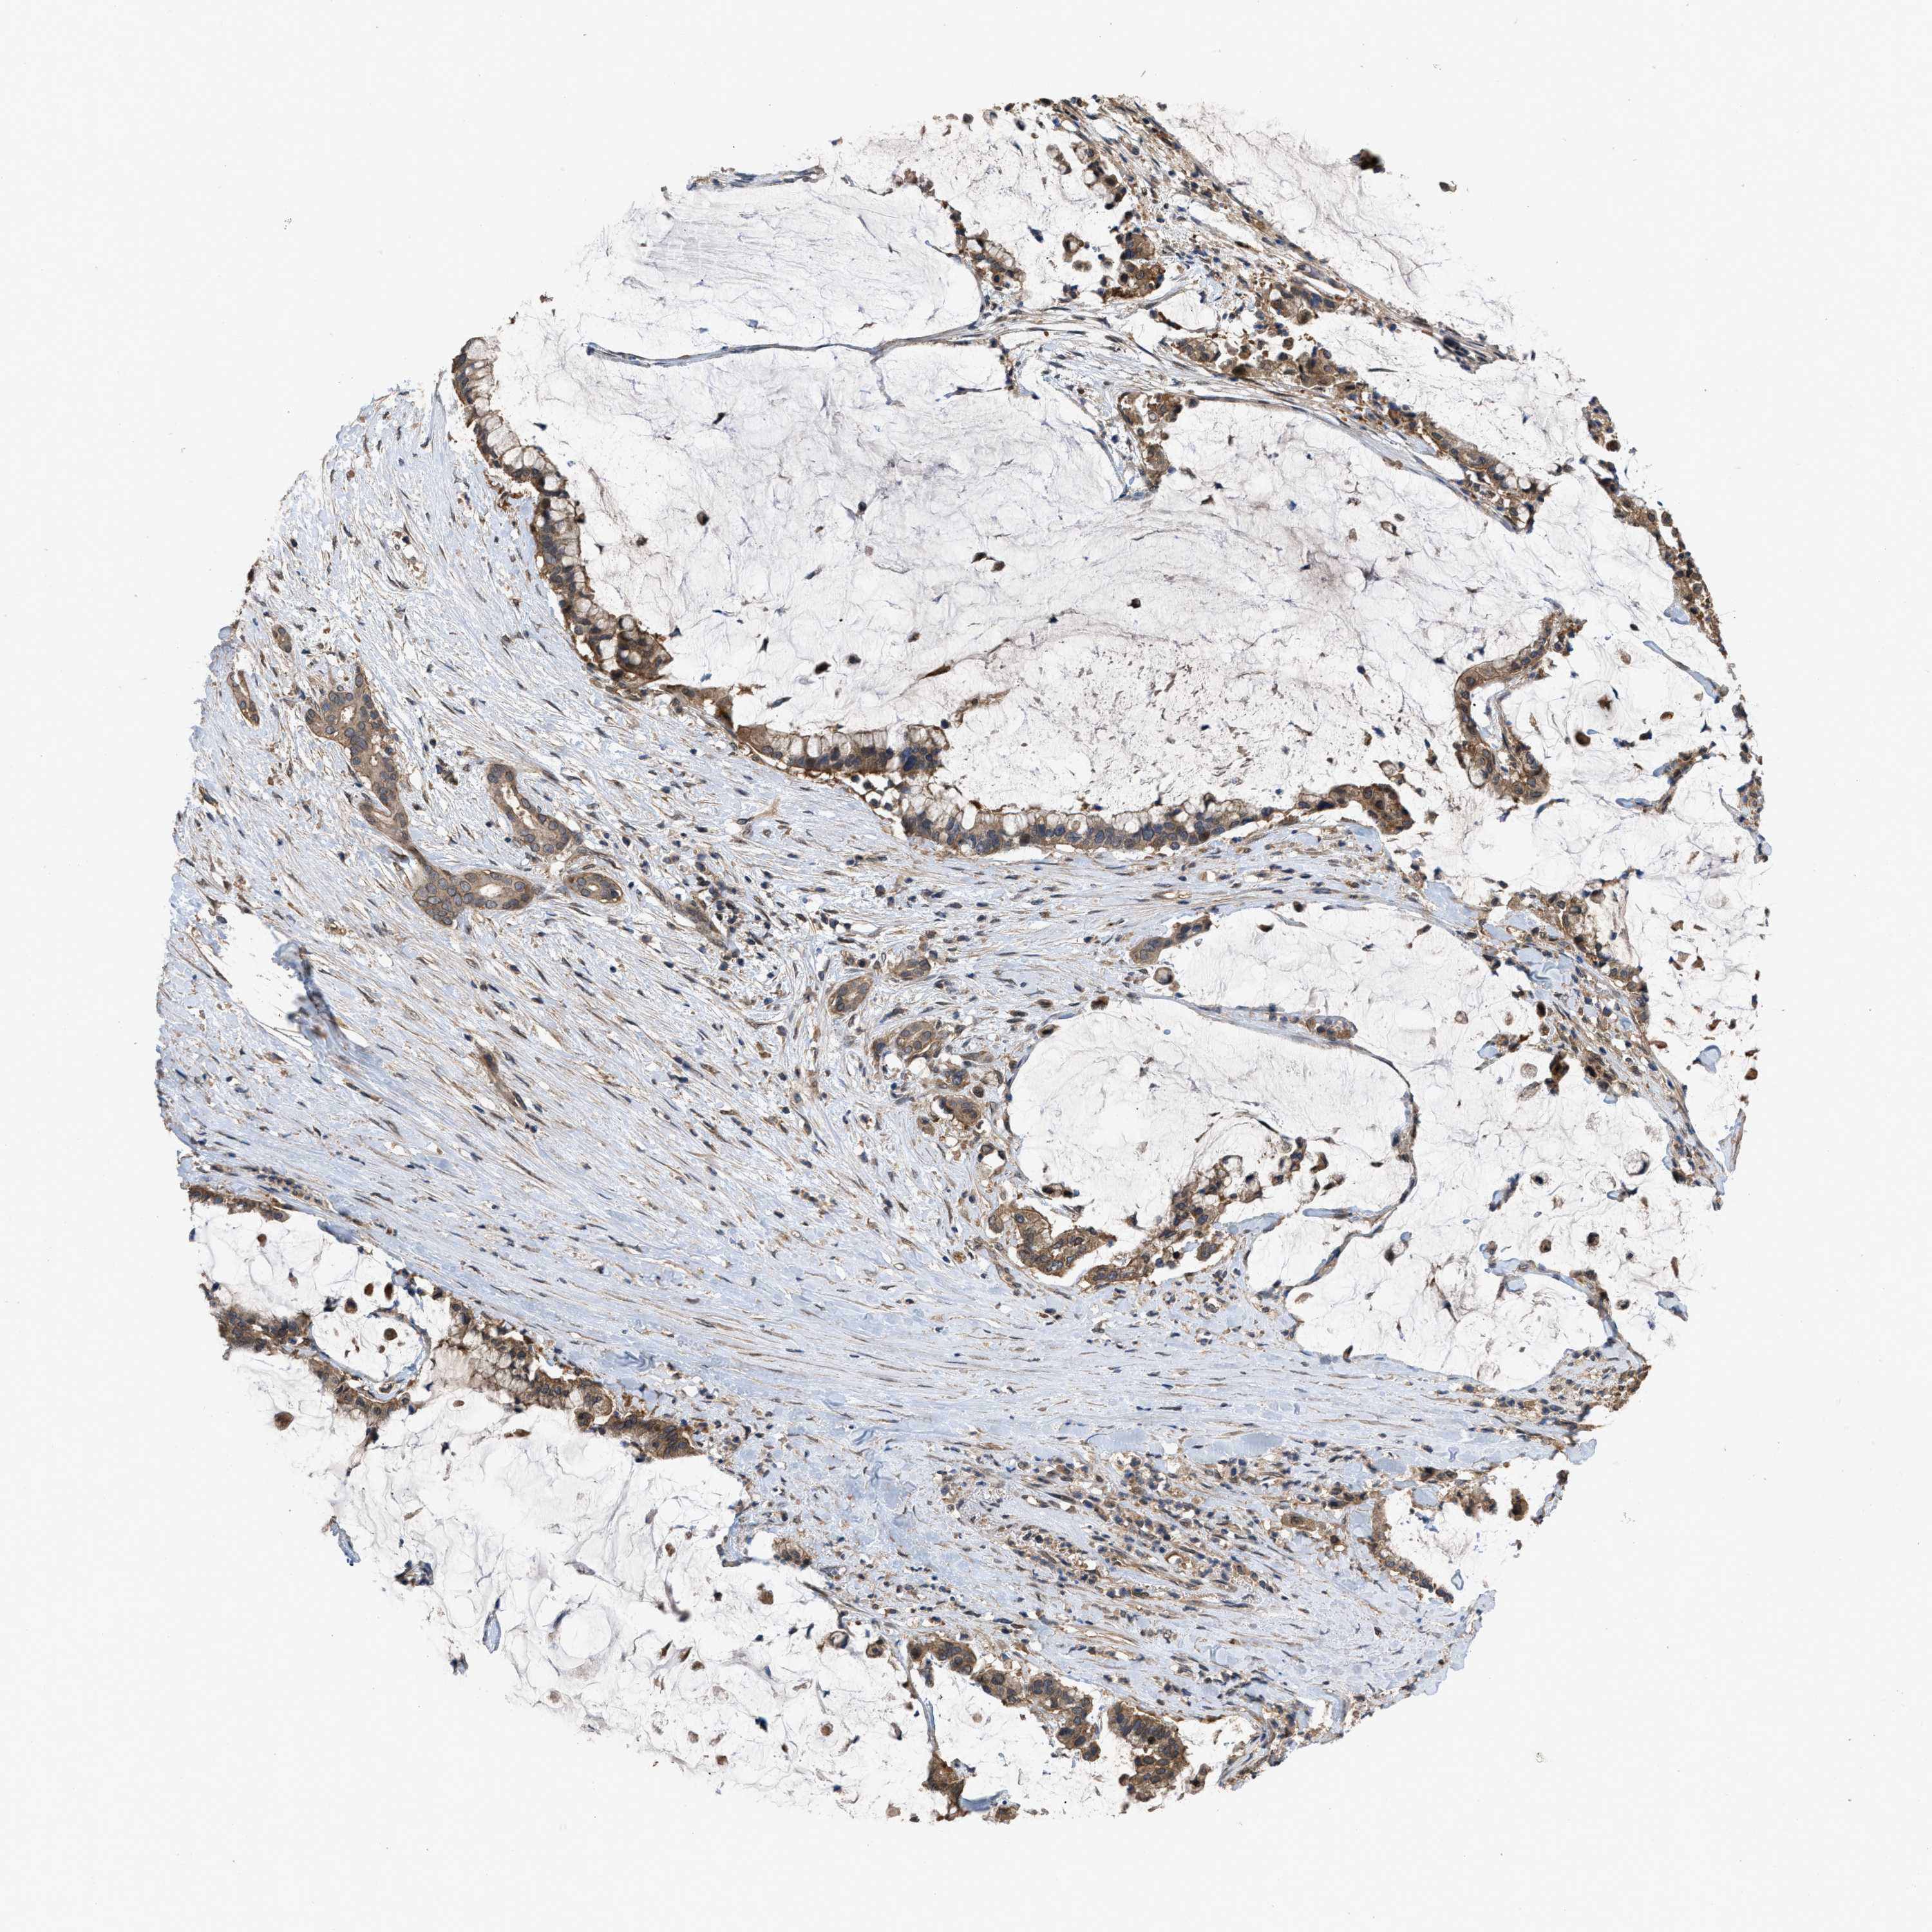

PANCREATIC CANCER - Protein expressioni

A mouse-over function shows sample information and annotation data. Click on an image to view it in a full screen mode. Samples can be filtered based on level of antibody staining by selecting one or several of the following categories: high, medium, low and not detected. The assay and annotation is described here.

Note that samples used for immunohistochemistry by the Human Protein Atlas do not correspond to samples in the TCGA dataset.

Antibody stainingi

Antibody staining in the annotated cell types in the current human tissue is reported as not detected, low, medium, or high, based on conventional immunohistochemistry profiling in selected tissues. This score is based on the combination of the staining intensity and fraction of stained cells.

Each image is clickable and will lead to virtual microscopy that enables deeper exploration of all samples and also displays staining intensity scores, fraction scores and subcellular localization as well as patient and tissue information for each sample.

Antibody HPA018894

Antibody CAB016348

Staining

High

Medium

Low

Not detected

Intensity

Strong

Moderate

Weak

Negative

Quantity

>75%

75%-25%

<25%

None

Location

Nuclear

Cytoplasmic/membranous

Cytoplasmic/membranous,nuclear

Adenocarcinoma, NOS